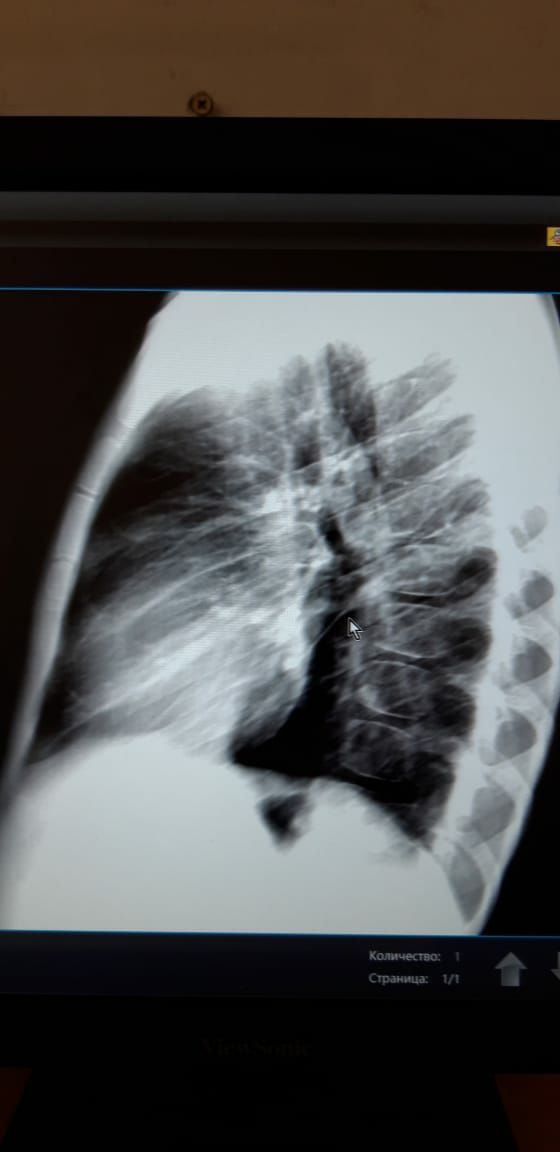

Здравствуйте ув. Коллеги! Посмотрите снимки ребенка мальчика 2016г. В крови от 5 июля-45 СОЭ. Неделю назад температурил. Сейчвс педиатр ставит ОРИ...Обследование... мы с Белой  Солт.решили что там с / долевая пневмония справа.....но никто кроме меня не видит овоидную тень  в С1-2?...я понимаю по этим снимкам трудно судить...но я сделала несколько с разной интенсивностью снимков... пожалуйста кто  что может посоветовать....мы решили пролечить и контроль...

Фото от 777